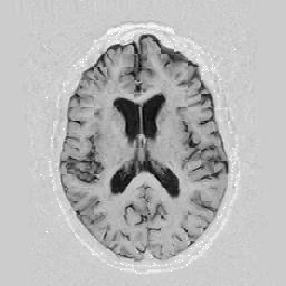

Another larger group of experiments enabled me to study the effects of multi-scale NRR. The results are shown in the form of chequerboard images in Figure [*]. In terms of resolution levels, higher numbers mean that the images are coarser.

Figure: Multi-scale NRR (increasing resolution). From left to right, top then bottom:before NRR; after 5 iterations of NRR at level 2 (higher is coarser); after another 5 iterations of NRR at level 1.